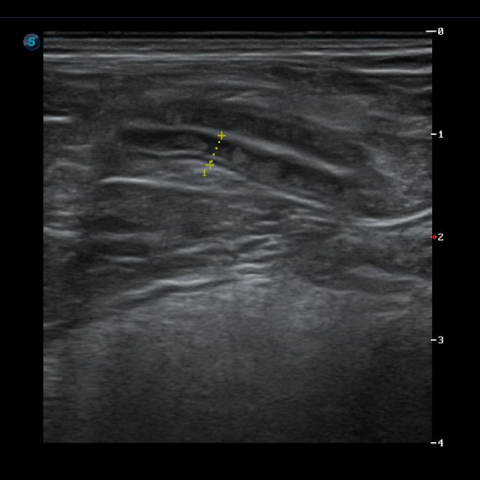

식이성, 특발성, 면역성 원인으로 생기는 췌장염은 구토, 설사, 식욕저하를 일으키고, 복통이 심한 질환 입니다. 다양한 기저질환에 의해 발생하여 만성화 되어 재발하는 경우가 많아서 만성적인 췌장염 관리와 합병증 관리가 필요합니다.

각 상황에 맞춰 분변검사, 혈액검사, 방사선검사, 초음파 검사를 진행합니다.

췌장염